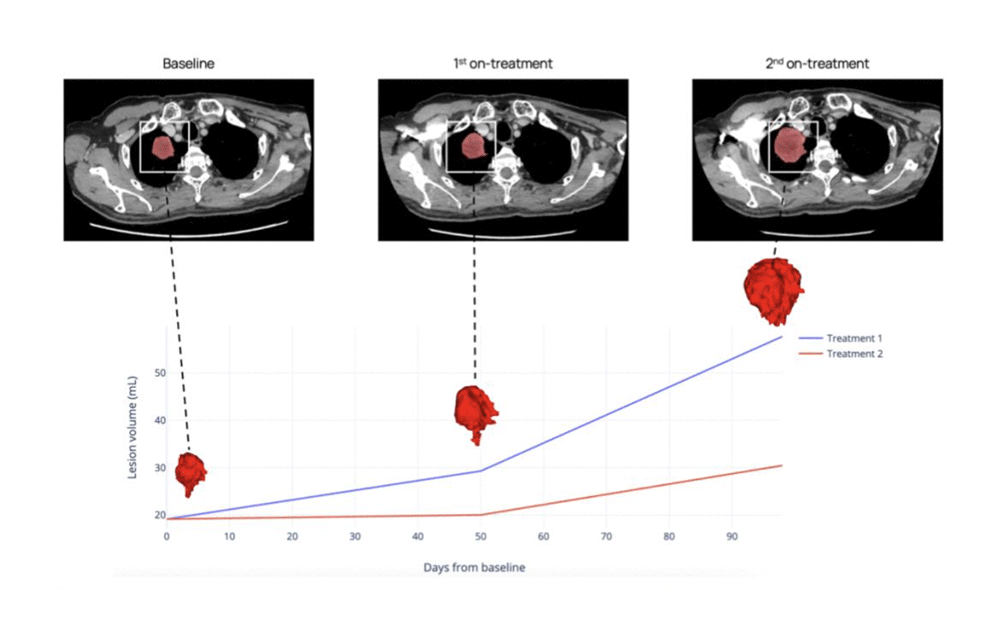

3. Tumor growth kinetics

Retrospective assessment and predictive simulations for individual lesions and tumor burden evolution provides insights into tumor evolution under multiple treatment arms. This capability allows researchers to model and compare treatment outcomes with unprecedented precision.

CT scans of a patient with advanced NSCLC showing target lesion evolution at three time points. This conceptual simulation illustrates how tumor growth kinetics and delta-radiomics can be assessed across treatment regimens. Not based on an actual predictive model.